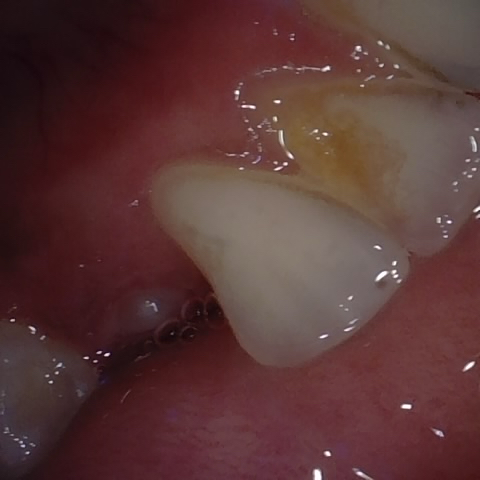

Image 160 / 400

NHD25466

Annotated as "Good"

Original Image Rendering Image